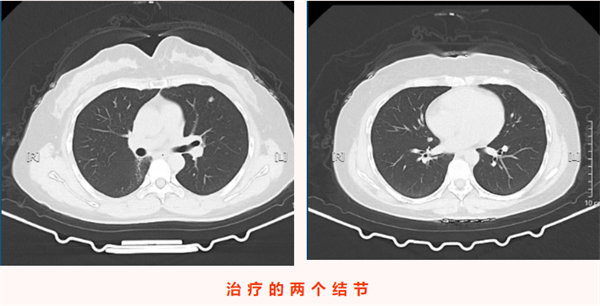

2025年11月24日,王女士的復查影像學檢查顯示:左肺上葉上舌段可見一大小僅0.8cm×0.5cm的微小實性結節,右肺斜裂處可見一0.7cm×0.6cm的實性結節,均為較前新增病灶。結合患者六年前氣管腺樣囊性癌病史,高度懷疑為轉移瘤。由于病灶性質不明且存在轉移可能,王女士為求進一步精準診療來到我院胸心腫瘤外科,門診以“左肺上葉繼發惡性腫瘤”將其收入院。值得注意的是,患者此次就診全程無咳嗽咳痰、發熱寒戰、胸悶氣短等任何典型癥狀,完全是通過規律復查發現的早期病灶,為后續干預贏得了有利時機。